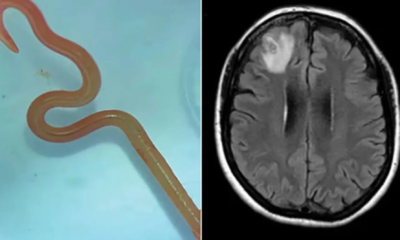

El gusano identificado como Ophidascaris robertsi suele vivir en el esófago y el estómago de las pitones diamantinas. Creen que la mujer tocó o ingirió una...